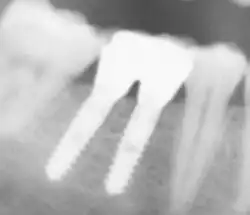

Ist der Zahn jedoch pulpitisch (entzündet) oder devital (abgestorben), muss er endodontisch behandelt werden, um (auch) eine entsprechende Pfeilerwertigkeit zu erlangen. Ein endodontisch behandelter Zahn ist spröder und damit bruchgefährdeter als ein vitaler Zahn. Das kann die Pfeilerwertigkeit reduzieren.[20] Nach einer Wurzelkanalbehandlung muss die Wurzelkanalfüllung bis zum physiologischen Apex (Wurzelspitze) reichen und randständig sein. Periapikale Entzündungen (im Knochen im Bereich der Wurzelspitze) führen zu einer Nichtverwertbarkeit des Zahnes, solange die Entzündung nicht abgeheilt oder durch eine Wurzelspitzenresektion (Kappung der Wurzelspitze) beseitigt worden ist.[21]

Implantate

Die Pfeilerwertigkeit von Implantaten entspricht bei ausreichendem Knochenangebot zur Verankerung (zirkulär ≥ 2 mm), nach einer vollständigen Osseointegration (Verknöcherung), ausreichender Länge (≥ 10 mm) und ausreichendem Durchmesser (≥ 4 mm), derjenigen eines gesunden, natürlichen Eckzahnes (Grad 1). Je nachdem, welche Abstriche bei den genannten Kriterien gemacht werden müssen, kann die Pfeilerwertigkeit von Implantaten entsprechend sinken.